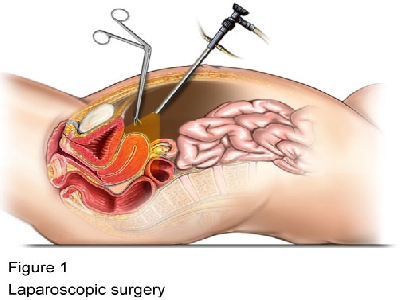

Endoscopy and Gynaecologic Surgery